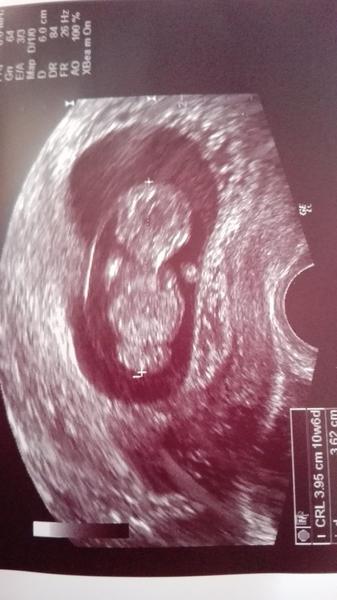

Tak já jsem konečně po kontrole 🙂 Nakonec je miminko starší,než jsem myslela (10+6tt) a má skoro 4cm 🙂 Příští týden nás čeká 1.screening a 9.2. 5D UTZ kvůli genetice.